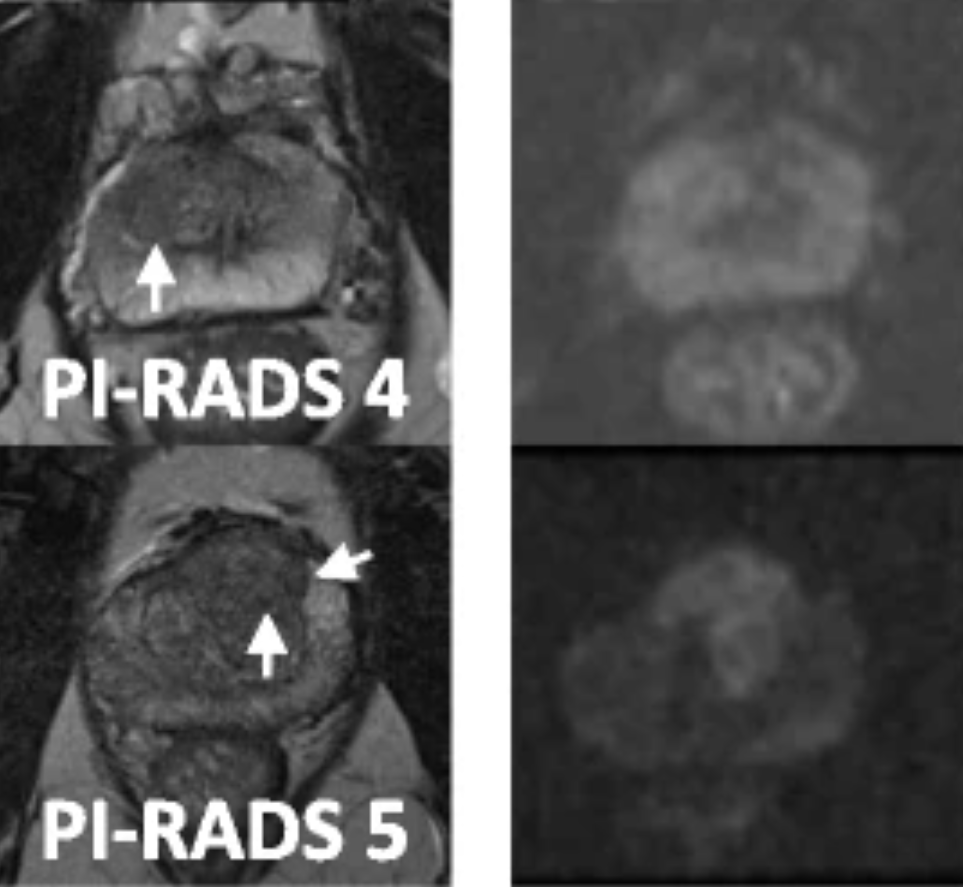

Led by Mr. Antoine Kass, A consultant Urologist in York, who performed thousands free hand TP biopsies, this course offers hands-on training in advanced transperineal prostate biopsy techniques.

Hands-on sessions with expert guidance, blending theory and practical experience seamlessly.